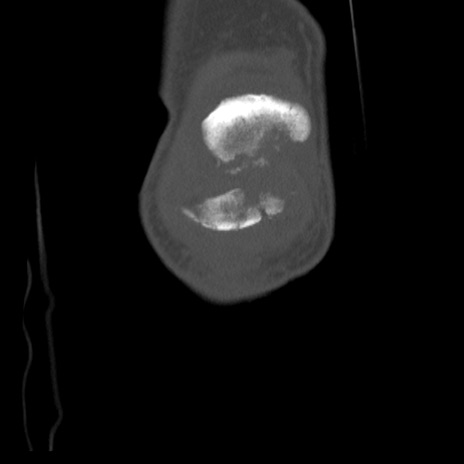

右膝関節CT

横断像